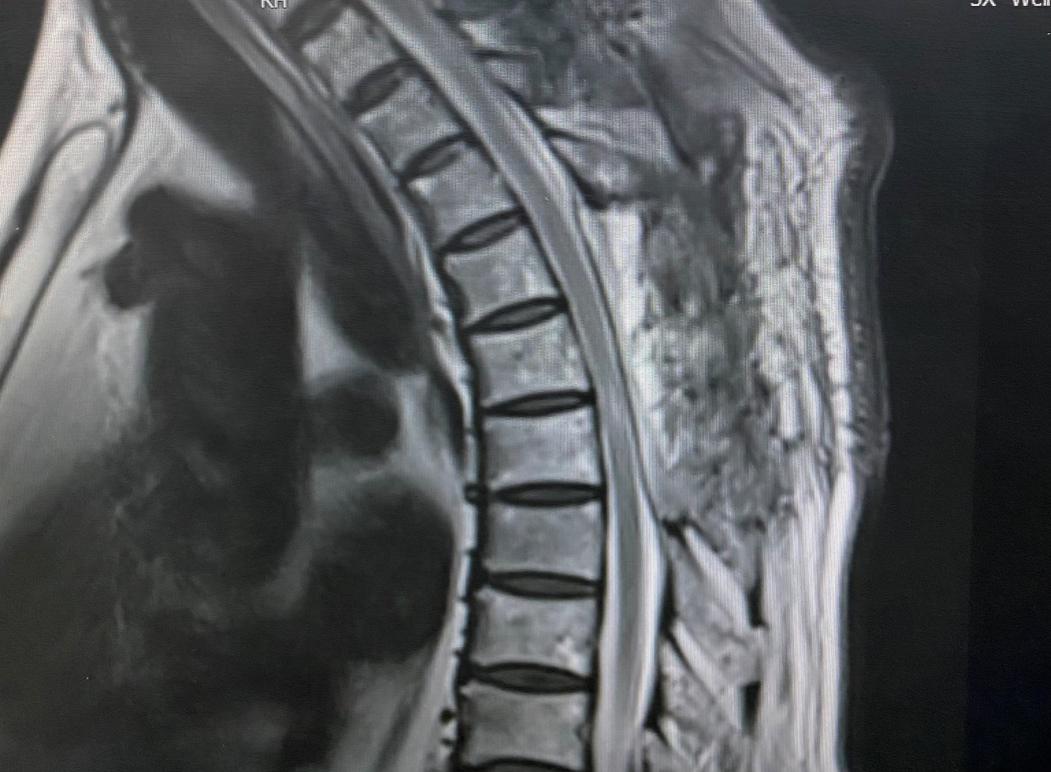

患者男性,66岁,1年前患者无明显诱因出现双下肢无力、麻木等症状,活动稍受限,多方治疗效果不佳。1月前,感足趾僵硬,并逐渐向上延伸至膝关节,同时伴小便失禁,查体见患者步态不稳、行走缓慢,步距小,踝关节及足趾跖屈力量减弱,脐以下感觉明显减退。入院后行胸椎MRI检查提示胸4-7椎体水平椎管内占位性病变,结合影像学资料综合考虑血管脂肪瘤。

主任白西民、副主任姚胜及支部书记党俊涛组织全科室人员讨论手术及围手术期治疗方案后,4月21日,由副主任医师冯毅主刀、主治医师赵云洁协助全麻下成功切除肿瘤。手术操作在显微镜下进行,真正实现了切口小、出血少、脊髓继发损伤轻微的手术预期。术后患者清醒并返回病房,即感双足僵硬感消失,足趾灵活性较术前明显改善,术后病理报告胸椎管内血管脂肪瘤。经科室医务人员精心治疗及护理后患者肌力逐渐恢复并好转出院。